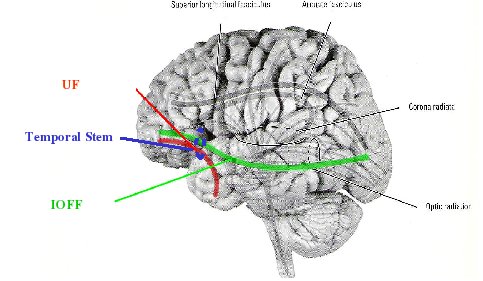

We followed up the ROI analysis of UF in chronic patients, in 27 chronic schizophrenics and 34 controls using a fiber-tracing method to estimate FA along the entire tract. We used two region-of-interest (ROI) extraction method, where we extracted fiber tracts traveling between two, manually drawn ROIs. First ROI was placed in the area previously investigated in our UF paper (Kubicki et al., 2002), second and third ROIs were placed within the temporal pole white matter, and posterior temporal white matter respectively. This resulted in two tracts, both traveling through the temporal stem, but separating their paths shortly after (Uncinate Fasciuclus (UF) and Inferior Occipito-Frontal Fasciuclus (IOFF)).